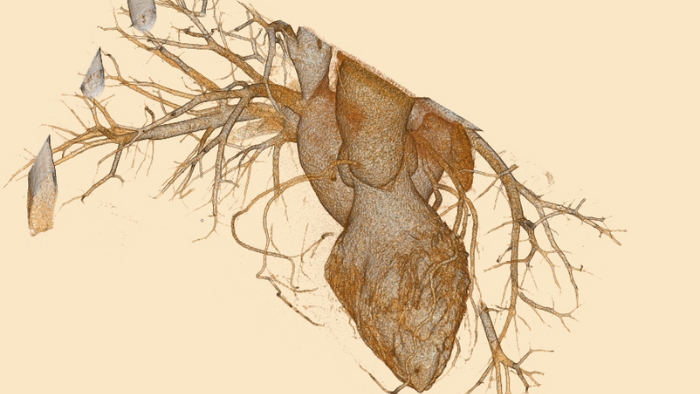

Erweitern Sie Ihre Einsatzbereiche in Bezug auf Herz- und Notfalldiagnostik/Trauma und eröffnen Sie neue Möglichkeiten für interventionelle und radioonkologische Prozeduren.

Die kardiologische Bildgebung erweitern und verbessern

Erweitern Sie die routinemäßige kardiologische Bildgebung durch die zusätzlichen klinischen Erkenntnisse der Spektraldetektor-CT für moderne kardiologische Anwendungen.